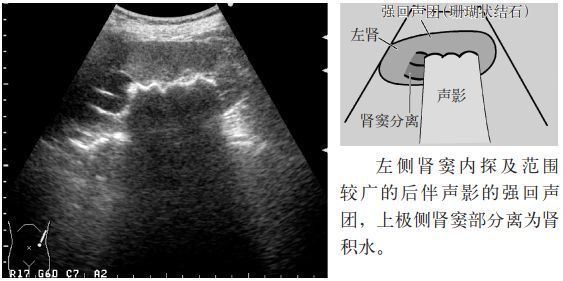

临床必备肾结石输尿管结石超声表现一览